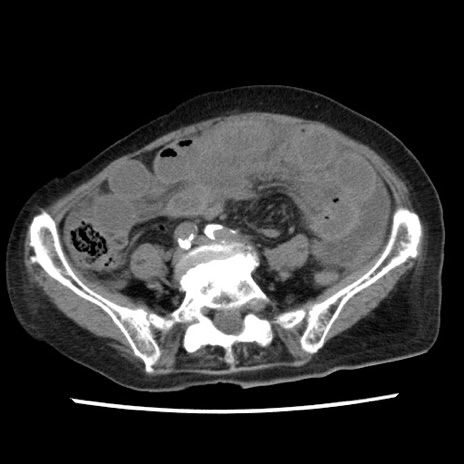

症例1(横断像)

【症例】80歳代女性

【主訴】腹痛

【現病歴】8時間前から腹痛あり来院。

【既往歴】糖尿病、脂質異常症、子宮体癌にて子宮全摘術

【身体所見】意識清明・会話良好だが腹痛で苦悶様、全腹部にわたって反跳痛と圧痛あり

【データ】WBC 13600、CRP 0.14、LDH 224、CK 90